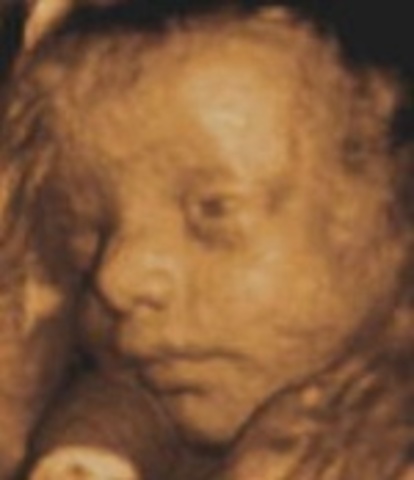

• Week 27: Eyes Open

Week 27: Eyes Open

At this point in the pregnancy, the mother and the baby are in their 3rd trimester. There is hair constantly growing on the baby such as head hair or eye lashes. The eyes are able to open and the baby is begining to become stout.